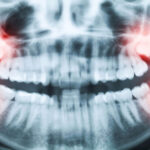

Bicuspids are known as permanent teeth that are located between the canine and the molars. In addition, premolars are also called Bicuspid teeth. These teeth appear before the molars appear in the mouth. The shape, or the crown of a bicuspid tooth, has two pointy edges (also called cusps).

We all have bicuspid teeth to chew and bite on food properly without taking in too much or little food in our mouths. These teeth are very similar to molars and canines, but they have an excellent chewing mechanism that is ideal for your mouth.